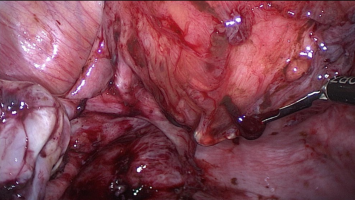

Operative Konzepte für die Therapie der Endometriose

Die operative Therapie der Endometriose ist anspruchsvoll. Sie reicht von der Resektion oberflächlicher peritonealer Herde bis zur interdisziplinären Operation mit partiellen Organresektionen an Darm, Blase, Urogenitaltrakt und Zwerchfell. Die …